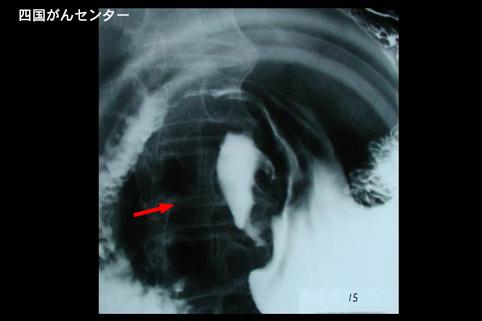

화학요법이 유효했던 위소세포암(내분비세포암) (증례제시:국립병원 시코쿠 암센터)

[Image-ID:3303]

위(부위)/전정

X-P

2형(궤양국한형)/

40이상